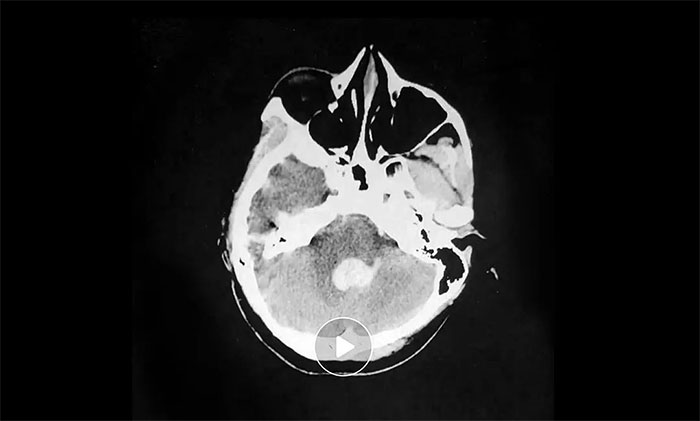

▲ 左侧大脑前、中动脉闭塞严

转入神经内科7A病区后,有着各类脑血管常见病、多发病及疑难病诊疗经验的张静波主任,进一步为小雨展开了详细检查。经影像学检查,其左侧大脑前、中动脉重度狭窄,造成左侧大脑半球重度低灌注,周围已有代偿性微血管网再通,符合“烟雾病”表现。

CT灌注成像(CTP)则显示,患者左侧大脑中动脉供血区存在大面积低灌注造成脑缺血,尤其左额叶和基底节区已存在血管性病变脑损害,缺血严重。

▲ 左侧大脑缺血严重

在阶段性的治疗下,脑出血业已得到良好控制,但患者仍存在意识障碍及右侧偏瘫。CTP也证实左侧大脑半球的大面积低灌注是导致意识障碍和右侧偏瘫的主要原因。幸运的是,低灌注区的脑细胞还有部分存活,没有发生坏死,如果及时恢复血供,还有存活的机会。